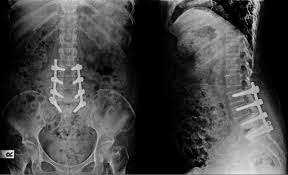

Spine surgery can fail if there is recurrence of slip disc even after disc removal surgery. This can occur either at the same level or some other level. Sometimes, spine surgery can fail due to failure to use spinal implants at the time of first surgery. Rarely, spine surgery can fail if the attempted union between the bones at the time of first surgery fails to materialize resulting in nonunion or implant failure. Another reason for failure of spine surgery can be progression of the degeneration in the spine to levels above and below the previously operated level.

Very commonly, we get patients with a failed previous spine surgery performed in their home country. We routinely perform revision surgery on such cases and ensure that their spine problem is solved and their problems are taken care of. To ensure maximum success in such complex cases we use new technology namely Carm, Pedicle screw instrumentation, High Speed Burr, Microscope, Navigation and Neuromonitoring to make even revision spine surgery highly successful. We have a lot of experience in dealing with such revision spine surgery cases and we can ensure successful outcomes even in these complex cases.